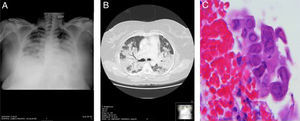

A 41-year-old woman, with no significant history, attended the emergency room with a 4-day history of fever, cough, bloody sputum, and dyspnea at rest. Physical examination revealed a temperature of 39.3°C; BP 100/50mmHg; pulse 101bpm. Of note on pulmonary auscultation were bibasilar crackles reaching the mid-fields. No other significant findings were noted. Clinical laboratory test results showed leukopenia with left shift, raised transaminases, and respiratory failure. Chest X-ray revealed extensive areas of bilateral lung disease, with air bronchogram in the right lung. (Fig. 1A). Chest computed tomography showed extensive pulmonary consolidation in both upper lobes and in the upper segments of the lower lobes, containing air bronchogram (Fig. 1B). The patient was admitted to the intensive care unit where she was intubated and mechanically ventilated. The bronchoalveolar lavage culture and polymerase chain reaction of bronchial secretion were positive for MRSA (>104CFU/ml) and influenza A (H1N1), respectively. During fiberoptic bronchoscopy, a biopsy was obtained from an infiltrating lesion observed in the entry to the middle lobe that showed extensive inflammatory changes with areas of ulceration. The report described abundant squamous cells with large, occasionally multiple, nuclei, with blurred chromatin (ground glass effect), and occasional isolated eosinophilic inclusions, consistent with HSV-1 infection (Fig. 1C), subsequently confirmed by polymerase chain reaction. Treatment was tailored to the antibiotic susceptibility test results (trimethoprim/sulfamethoxazole and levofloxacin), and oseltamivir and acyclovir were added. The patient's progress was favorable, chest X-ray normalized, and she was discharged a few weeks later.

(A) Chest X-ray in decubitus position showing extensive areas of bilateral consolidation. (B) Chest computed tomography showing extensive lung consolidation containing air bronchogram. (C) Bronchial biopsy specimen showing squamous cells with enlarged, occasionally multiple, nuclei, with blurred chromatin (ground glass effect), typical of herpes virus infection (H.E. 400×).